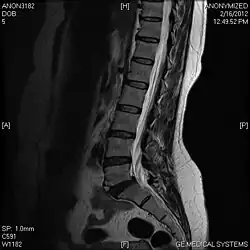

T1 W Sagittal

Limbus Vertebra L5